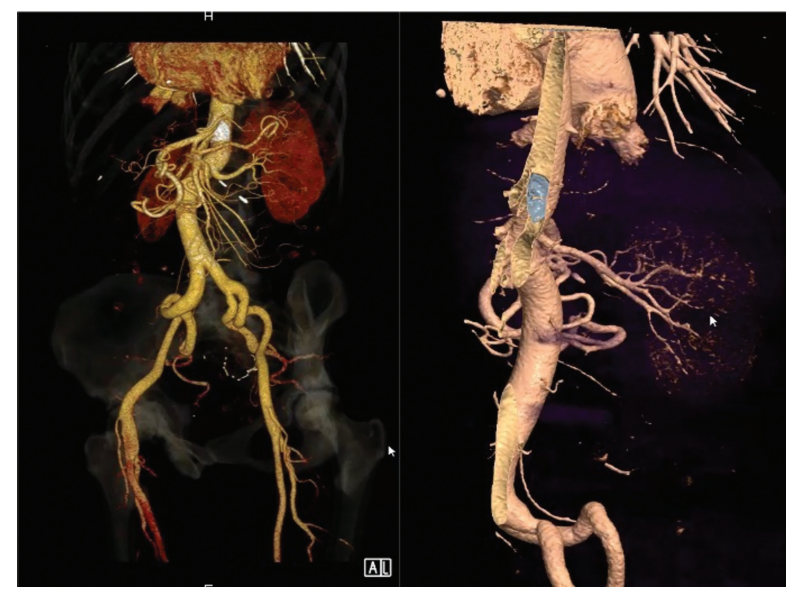

胸部和腹部计算机断层扫描(CT)显示封堵器移位并栓塞至肠系膜上动脉,导致其完全闭塞,但有重要的侧支循环过程,没有器官缺血或症状的迹象(►图2)。患者向作者所在中心咨询了微创手术方法。采用腹股沟插管进行体外循环(CPB)的经典微创方法在建立通过股动脉的逆行CPB血流后,因封堵器再脱位的风险而受到挑战。因此,作者决定采用中央动脉插管和外周静脉引流的微创前胸手术。

图2. 计算机断层扫描的数字重建显示了肠系膜上动脉完全闭塞后腹部血管侧支化的重要过程(封堵器用白色表示)。